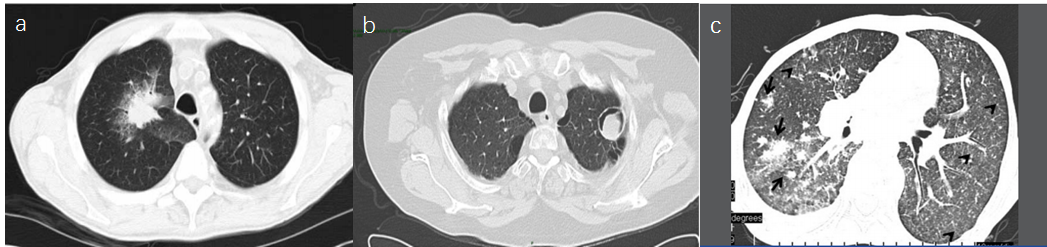

若化疗后粒细胞缺乏或移植后患者出现肺部典型的晕征新月征空洞,首先要考虑患者是否感染曲霉[1]。侵袭性曲霉病的影像学特征是“晕征”,特别是中性粒细胞减少患者,表现为一个直径>1厘米的中心结节,周围有反映出血的毛玻璃影,如图1a[3]。通常在疾病进展两周后,出现“空气新月征”,如图1b[4]。气管支气管炎的CT表现通常为气管支气管壁增厚,存在小叶中心微结节,为“树芽征”,如图1c[5]

图2 CT表现(a晕征; b空气新月征; c树芽征)

肺隐球菌病影像学表现主要分为4种类型:肿块或结节影、单发或多发斑片影、结节与斑片影混合病灶、弥散性粟粒影[6],其中结节型最为多见。结节型肺隐球菌病较常分布于胸膜下,空气支气管征晕征分叶是相对具有鉴别性的CT表现(如图3),其临床和CT表现均缺少特异性且复杂多变,极易误诊为肺结核、周围型肺癌、炎性假瘤[7]。肺隐球菌病病理改变与机体自身免疫状况有很大关联。免疫功能较完善者易在肺内形成肉芽肿,病灶中可出现干酪样坏死并形成空洞,主要为单发病灶,位置以肺周边为主,主要提示为结节、肿块。免疫功能缺陷者的病灶周围易发生炎性反应、肺泡实变、多发结节和斑片影,提示为肺内播散病灶[6]。

图3 CT表现(a支气管充气征; b肺隐球菌病晕征; c多发结节周围磨玻璃影)